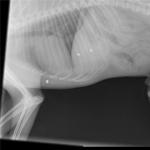

4 дня назад, ночью в моем дворе, какой-то урод стрелял в мою собаку. 3 пули. Одна из них попала в печень, две остались за диафрагмой в грудной области.

Ту что попала в печень достали, но печень при операции пострадала. Две другие не смогли т.к. у нас в Бресте нет клиник оперирующих грудную полость.

Завтра могу запостить снимки рентгеновские.

снимки пуль уже ниего не значат- печень отказывается работать.

Добрый вечер! Пулек осталось две. Та, что в районе грудной кости не опасна вообще - она не задела ничего и не вошла в грудную полость, застряв в области грудных мышц, кроме того, миграция возможна только вниз, образуется абсцесс, вскроется, всё разрешится само-собой.

Пуля в районе 7 или 8-го ребра опаснее, но: лёгкое не задето (по крайне мере Вы не упоминали о симптомах лёгочного кровотечения), пневмоторакс то же под большим вопросом (вспомните - были кровавые пузыри в такт дыханию над дыркой?), значит велик шанс, что не пробита рёберная плевра, если так - инородного тела в грудной полости нет и эта пулька не опаснее первой. Судя по тому, что Вы пишете - воспаления нет и болевого синдрома то же, а значит всё стоит на месте. Моё мнение - так и будет дальше. Сделайте ещё раз снимок через 3-4 недели, если не будет плеврита и пуля будет на месте - я бы у своей собаки продолжал просто наблюдать.